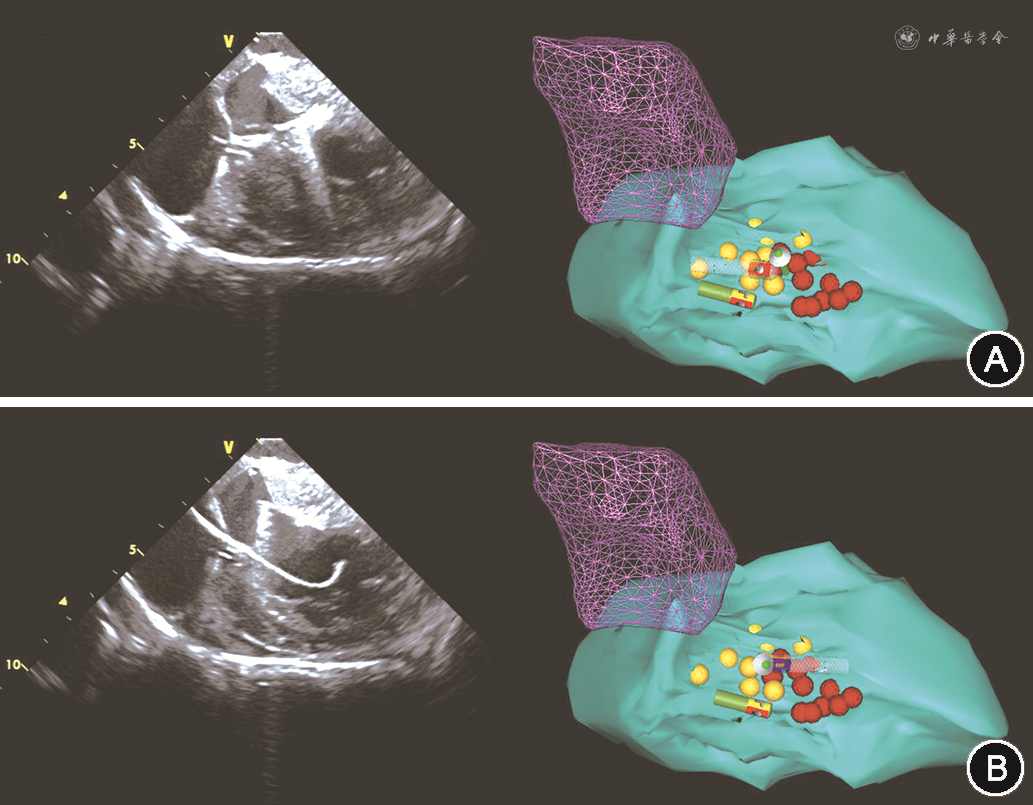

如HOCM诊断无误后,则经左侧股静脉置入心腔内超声导管(美国Biosense Webster公司,规格型号:CartoSound)行左右心室以及流出道等结构的三维重建,重点重建左心室流出道、室间隔以及二尖瓣后叶,并在左心室长轴切面观察二尖瓣收缩期前向运动(SAM征)(图2)。完成超声指导的心腔三维重建后,经右侧股动脉经主动脉逆行途径送入4 mm冷盐水灌注导管(美国Biosense Webster公司,规格型号:Navi-Star Thermo-CoolTM)至左心室,在Carto3标测系统指导下首先在原左心室解剖上标记His束以及分支走形的空间位置(图3)。随后超声扇面调整至与左心室长轴平行以显露梗阻位置,顺时针转动消融导管贴靠室间隔。使用40 W功率模式(初始盐水流速20 ml/min,温度上限45 ℃)逐点放电消融,保证压力贴靠在10~15 g,每点放电时间40 s(图4)。在完成10~15个局灶消融点,同时心腔内超声提示局部(最厚)室间隔处回声增强且梗阻解除(SAM征消失)后撤出消融导管,复测LVOTG。如复测LVOTG不满意,则在原消融部位及周边巩固消融放电10~12次后结束手术。

注:绿色结构为左心室;暗紫色网格结构为主动脉窦

注:绿色结构为左心室;暗紫色网格结构为主动脉窦;黄色为可记录到束支电位点;红色为消融点